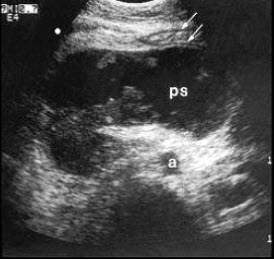

10、单项选择题

某患者右下腹痛,血尿,根据超声声像图,最可能的诊断为()

A.右肾结石

B.右输尿管下段结石

C.阑尾炎

D.膀胱结石

E.输尿管肿瘤